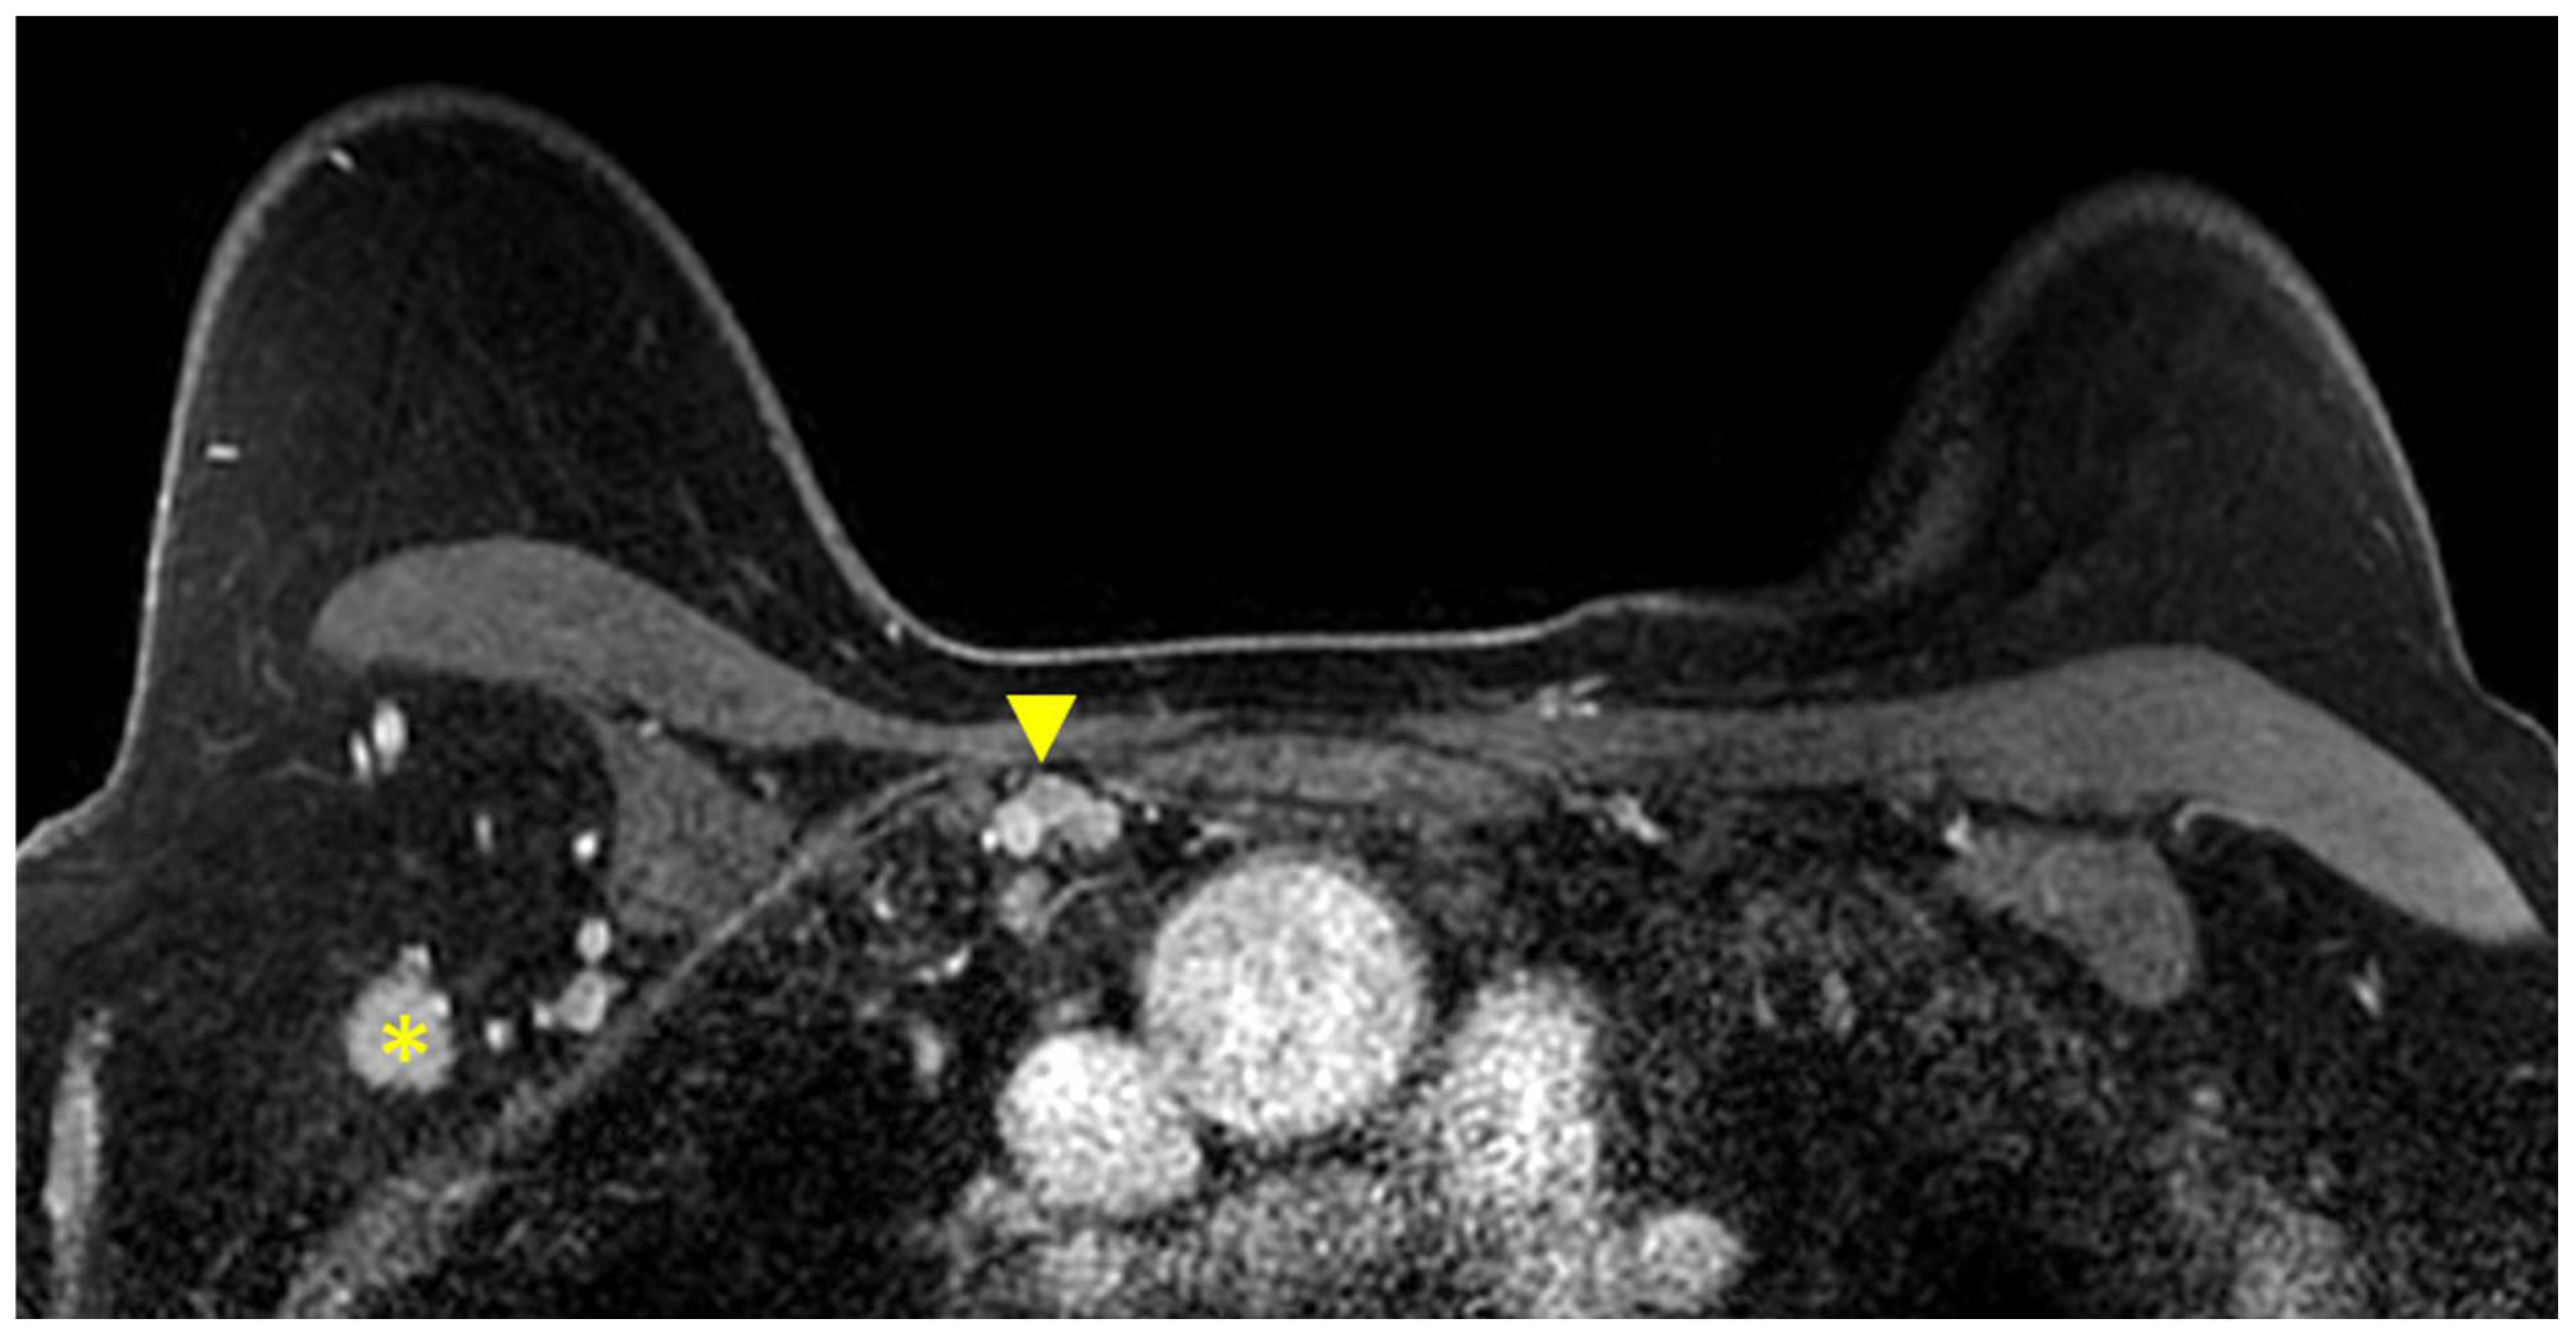

3.1.6. Evaluation of Internal Mammary Lymph Nodes (IMLNs)

- Behzadi, S.T.; Moser, R.; Kiesl, S.; Nano, J.; Peeken, J.C.; Fischer, J.C.; Fallenberg, E.M.; Huber, T.; Haller, B.; Klein, E.; et al. Tumor Contact With Internal Mammary Perforator Vessels as Risk Factor for Gross Internal Mammary Lymph Node Involvement in Patients With Breast Cancer. Int. J. Radiat. Oncol. Biol. Phys. 2024in press. [CrossRef] [PubMed]